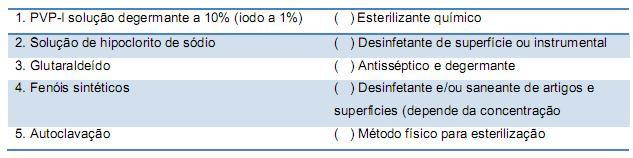

A limpeza do local de trabalho deve ser realizada, regular e imediatamente, após o término de uma atividade. Essa tarefa é essencial para reduzir os riscos de contaminação acidental pelo técnico ou outro indivíduo presente no local.

Numere a coluna da direita com base na informação da coluna da esquerda.

A sequência CORRETA, de cima para baixo, é:

Numere a coluna da direita com base na informação da coluna da esquerda.

A sequência CORRETA, de cima para baixo, é: